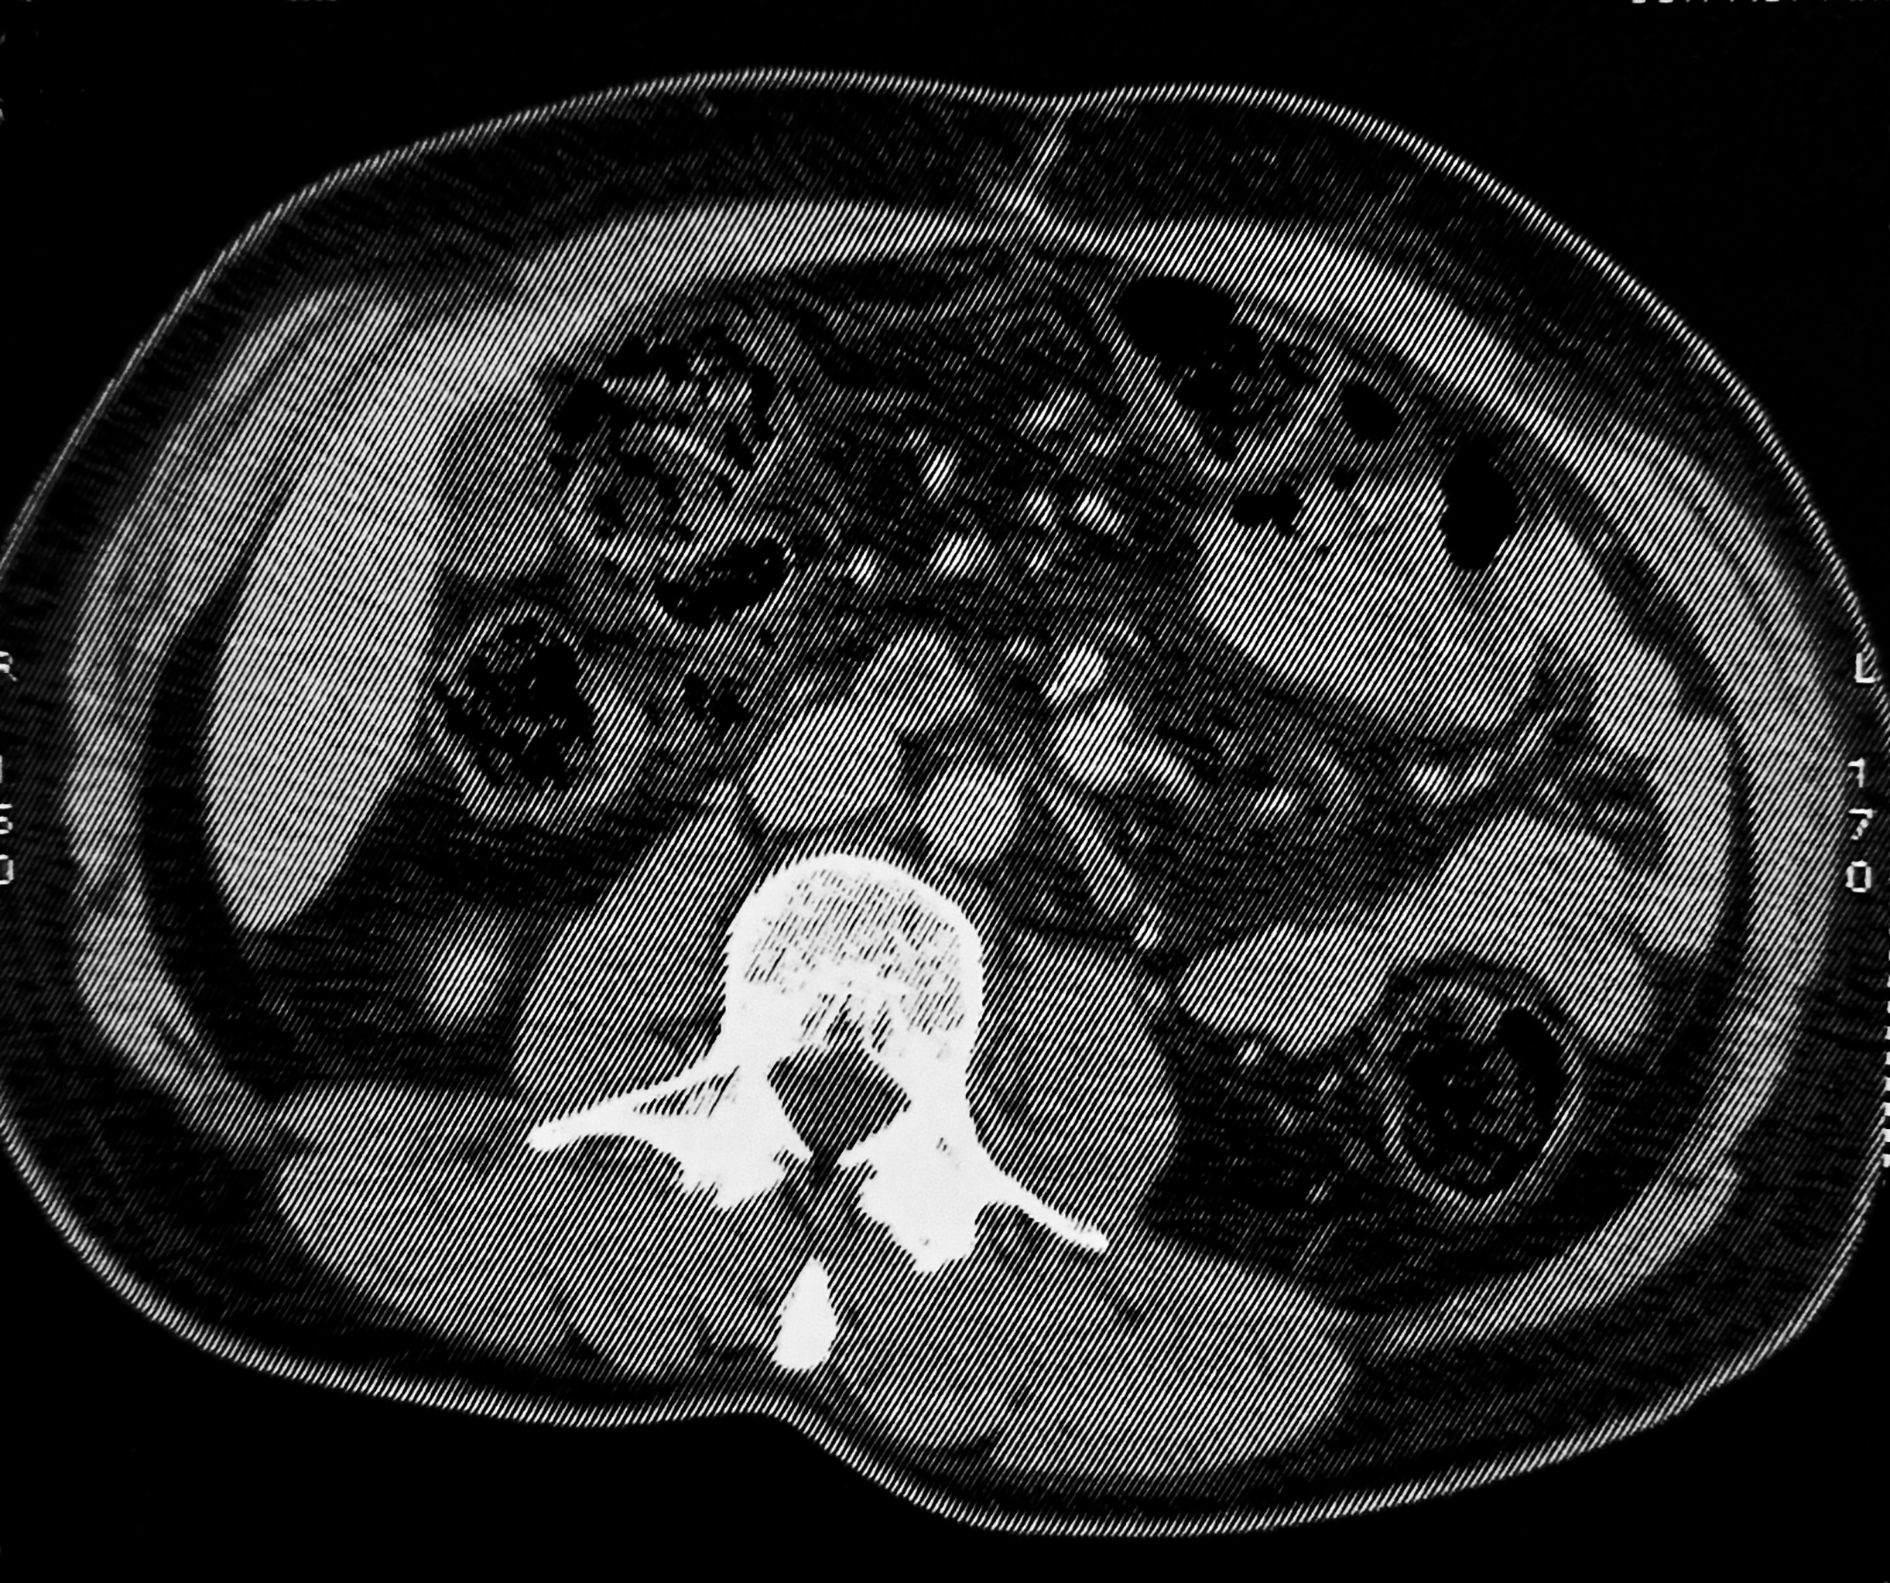

A thoraco-abdomino-pelvic CT scan revealed new, non-necrotic lymphadenopathy at the aortic bifurcation (22 × 9 mm) and in both internal iliac chains ( Figure 3).